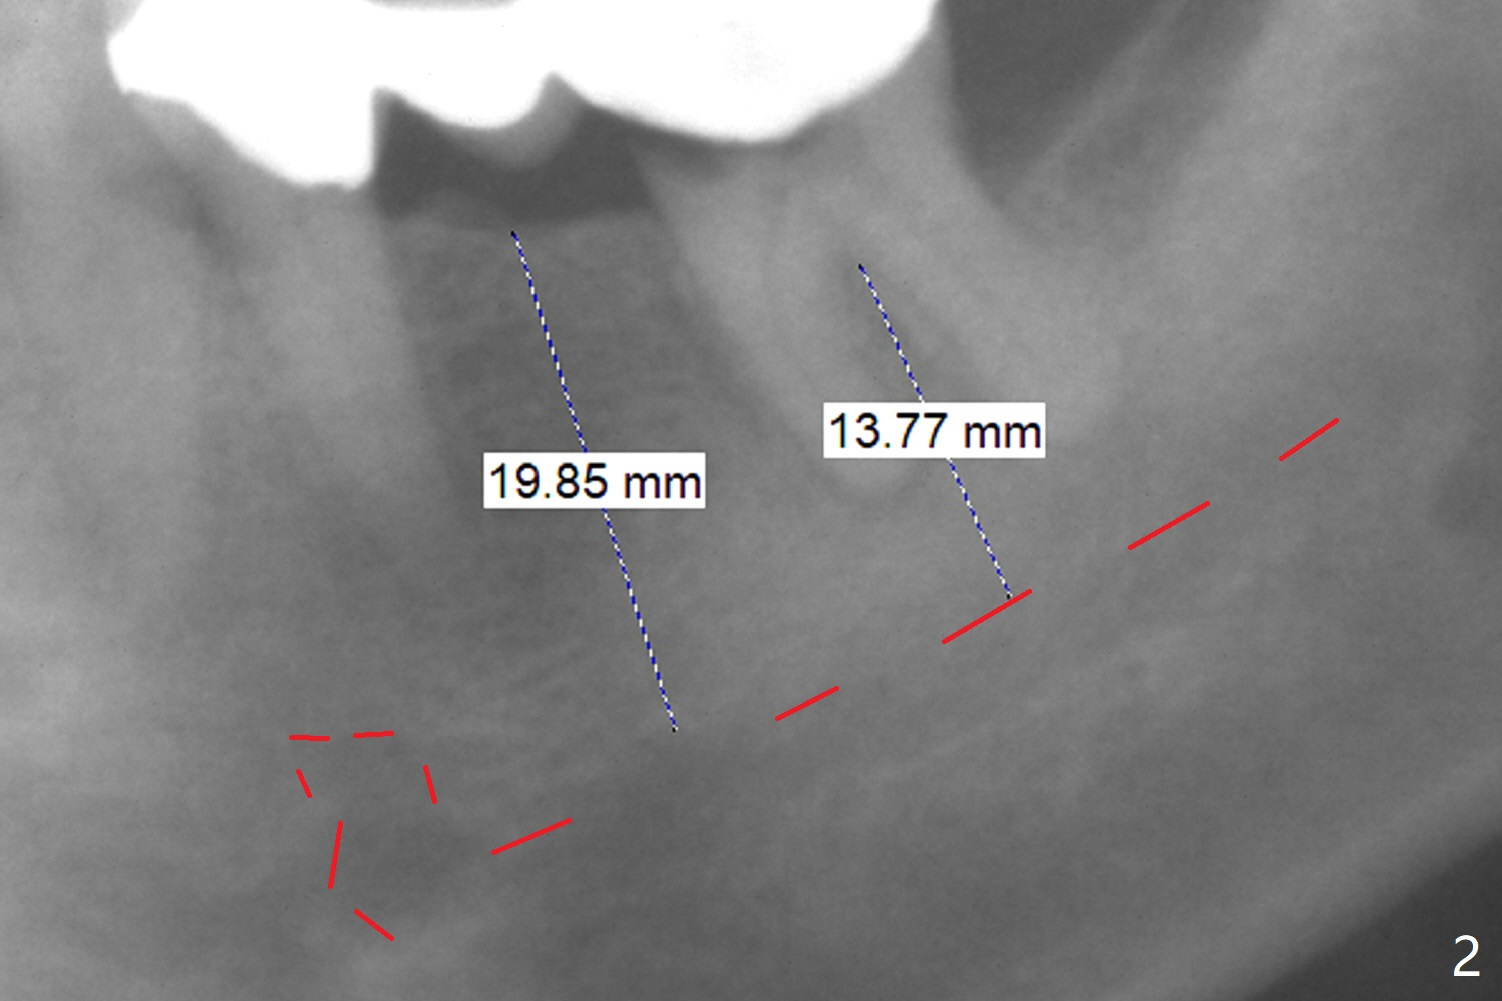

A 63-year-old man has lots of restoration (Fig.1), including #18-20 3-unit FPD. The latter has been sectioned to confirm non-salvageability of the tooth #18. After extraction and debridement, use a Rongeur purchased recently to flatten the pointed septum if present. Osteotomy is initiated with 1.6 mm and 2 mm pilot drills (parallel pin, PA), followed by sequential Magic Drills. If the septum is absent, use IS short stoppers to make osteotomy in the native bone (from the bottom of the socket). An incision will be made at the site of #19. If the edentulous ridge turns out to be narrow, choose a 1-piece implant. Otherwise use a Magicore. Take photos of the tooth #18 prior to extraction.